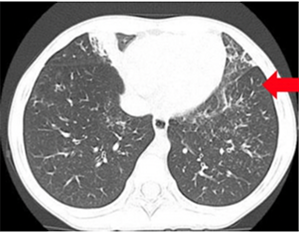

当院では、仮想気管支内視鏡検査は肺と気管支が一度に評価可能です。

仮想気管支内視鏡

CTによる仮想気管支内視鏡検査肺と気管支の評価が一度に可能です。